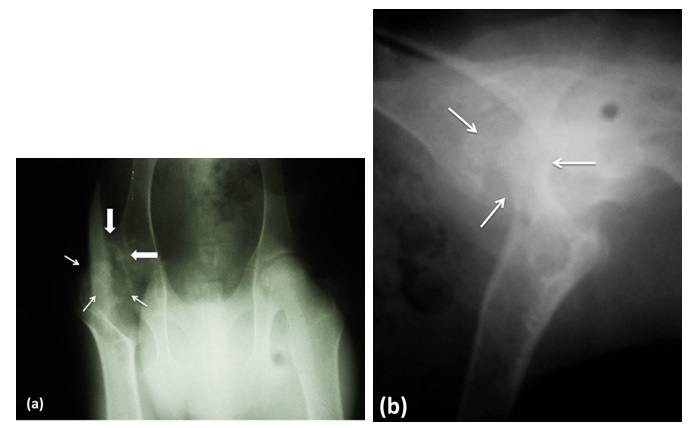

Diagnostic help. In order to complement the clinical diagnosis, pelvic radiographs were performed in two incidences (middle lateral and ventro dorsal). The right coxal articulation showed: increased joint space, irregular shape of the femoral head and neck and periarticular osteophytosis (Figure 2).

In this case, the simple radiography was the tool used to approximate the diagnosis of AVNFH, which showed irregular bone density and degenerative changes typical of osteonecrosis of the head and neck of the femur. Radiologically, signs of osteonecrosis were observed, with a decrease in the radio-density of the femoral head and abnormal contours of the same (1). These findings agree with the findings available in experimental studies in goats and sheep (12).